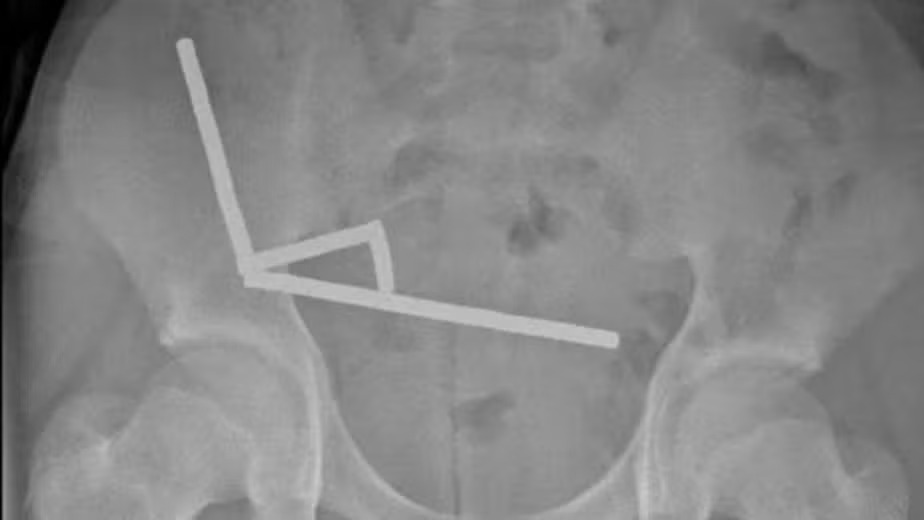

Os exames mostraram que os ímãs haviam se agrupado em quatro pontos distintos do abdômen, obrigando os médicos a realizar uma cirurgia de urgência. Parte do intestino delgado e grosso precisou ser removida. O menino permaneceu hospitalizado por oito dias até receber alta.